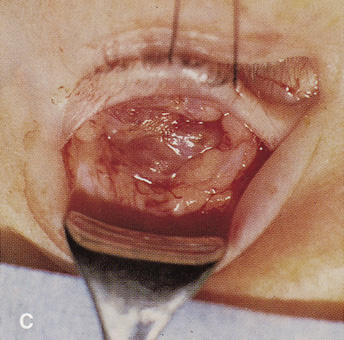

Procedure

A frontoethmoidal, or Lynch, skin incision is marked halfway between the medial canthus and bridge of the nose. It extends superiorly and inferiorly in a curved fashion approximately 2 to 3 cm (Fig. 16). The exact limits of the incision depend on the location of the underlying lesion. Injection of local anesthetic with epinephrine provides vasoconstriction, which greatly enhances hemostasis. After the skin is incised, a unipolar cutting cautery is used to extend the incision deeply to the periosteum. Bleeding may be encountered, especially in the area of the angular artery and vein. Exposure is enhanced with 4-0 silk sutures passed into the orbicularis muscle and clamped to the drapes.

Fig. 16. A. Patient with right orbital cellulitis. B. Coronal CT scan demonstrating subperiosteal abscess formation from frontal and ethmoidal sinusitis. C. Frontoethmoidal orbitotomy incision marked for abscess drainage.

The periosteum is exposed and incised with a Freer elevator and then is reflected off the bone posteriorly. It is generally quite adherent to the curved contour of the medial canthal bones, especially at the medial canthal tendon. The anterior lacrimal crest is encountered inferiorly. Care should be taken not to damage the lacrimal sac with the elevator. The posterior lacrimal crest is visible behind the sac. Adequate mobilization of the periosteal connections to the anterior lacrimal crest gives a large area of exposure. The periosteal elevation is carried superiorly in the area of the trochlea. Elevation of the periosteum opens the subperiosteal space. Blood or pus caused by fracture or infection, if present in this space, is encountered at this point.